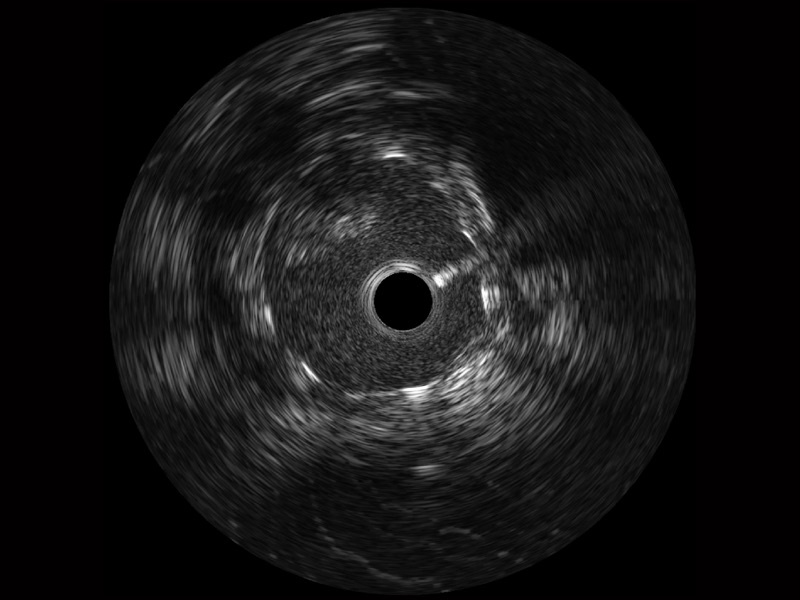

• 美狮贵宾会官网宽频IVUS图像

对比传统IVUS导管成像,美狮贵宾会官网宽频IVUS图像的近场支架梁显影更细腻,远场中膜外血管仍清晰可辨,兼顾远中近,兼顾分辨力与穿透深度